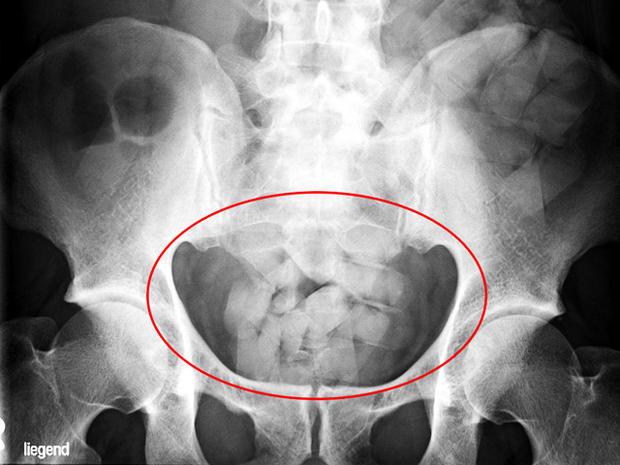

第三名毒贩是一名刚果籍男子利用身体运毒,他被送到医院进行X光检查后,扫描显示他的胃中藏有毒品包装物,经排出后检测,是为可卡因。